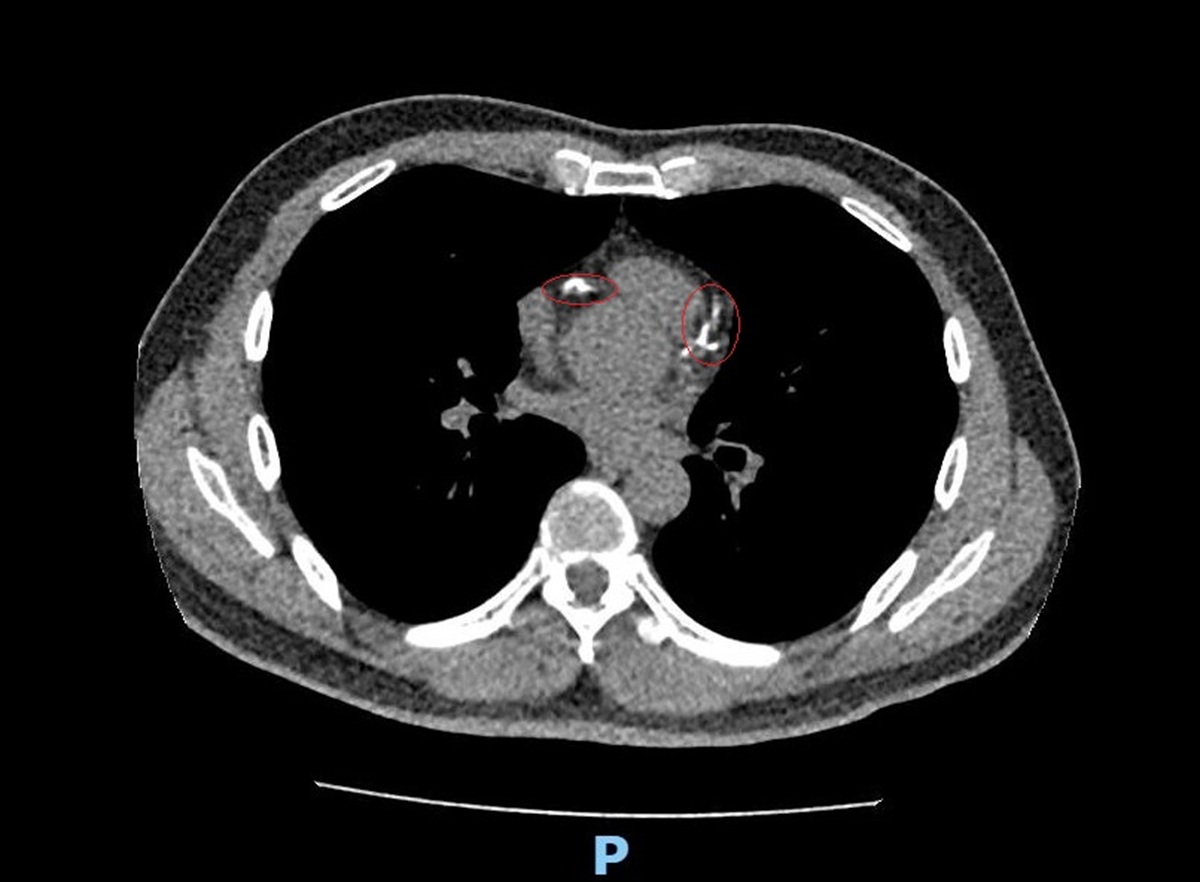

李學林表示,林先生日前接受肺癌篩檢時意外發現心血管鈣化,但無法確認是血管內或血管外鈣化。因患者平時已出現胸悶症狀,進一步做心臟冠狀動脈電腦斷層,確認為3條主要冠狀動脈血管內鈣化狹窄達85%以上,若未及時處理,隨時可能引發急性心肌梗塞。

▲李學林表示,林先生日前接受肺癌篩檢時意外發現心血管鈣化,但無法確認是血管內或血管外鈣化。(圖/彰化醫院提供)